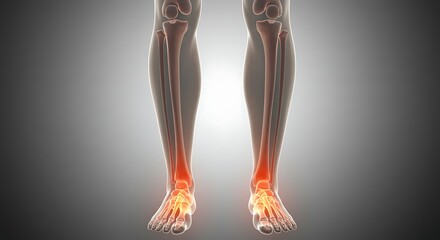

Podobny obraz Medical Elbow Anterior View X-Ray Radiograph Illustrating...